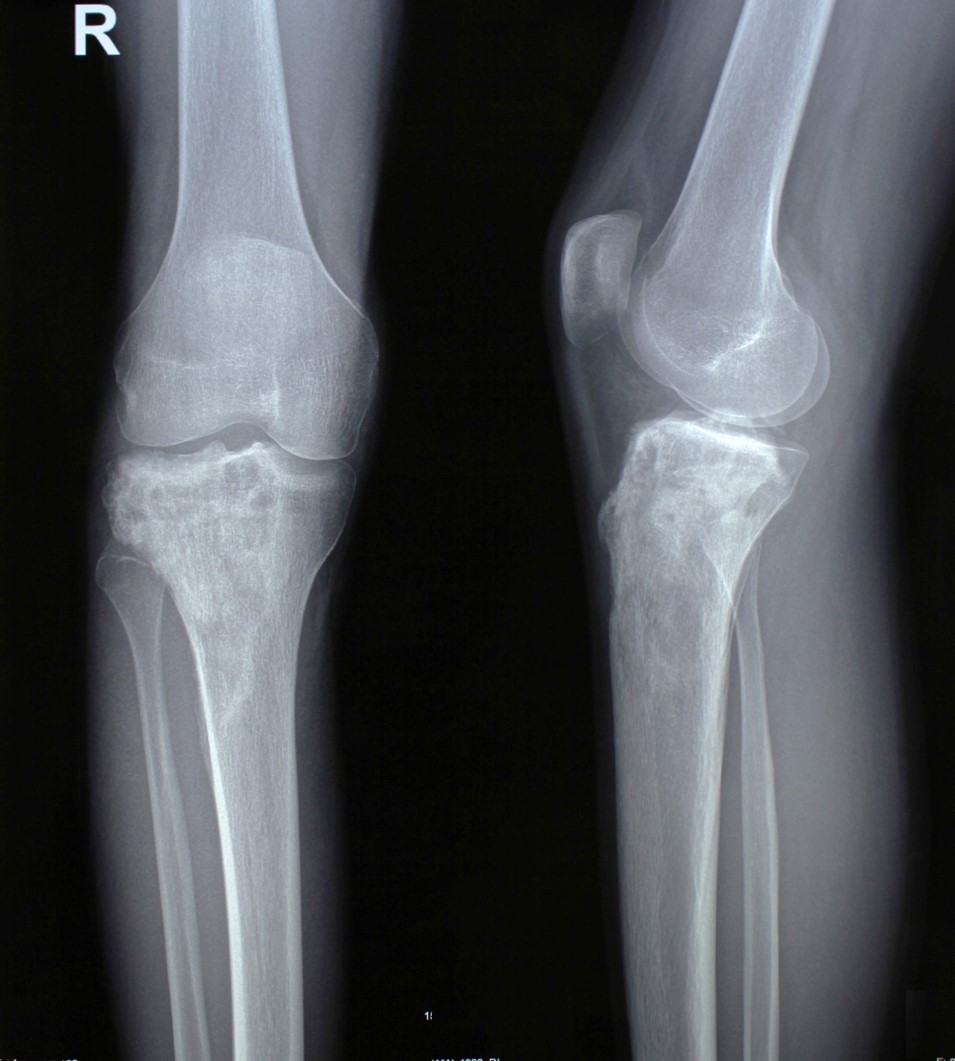

2. Բժշկական տարբեր կենտրոններում հետազոտվելուց հետո՝ 17-ամյա պատանին դիմել է «Նաիրի» ԲԿ։ Համապատասխան հետազոտություններ անցնելուց հետո՝ բուժառուի մոտ հայտնաբերվել է ոլոքի օստեոսարկոմա (ոսկրային քաղցկեղ): Նախավիրահատական բուժում ՝ քիմիոթերապիա, ստանալուց հետո՝ «Նաիրի» ԲԿ ում կատարվել է օրգանապահպան վիրահատություն : Հեռացվել են ծնկահոդն ու ոլոքի վերին երորդականը: Առաջացած դեֆորմացիան շտկել է Եվրոպայից պատվիրված էդոպրոթեզով, որը հնարավորություն է տվել պահպանել վերջույթի գործառույթը՝ քայլել, վազել և այլն։ Հետվիրահատական շրջանում բուժառուն ստացել է քիմիոթերապիա։ Այժմ գտնվում է բժիշկների հսկողության ներքո։

Վիրահատությունից առաջ

Վիրահատությունից հետո